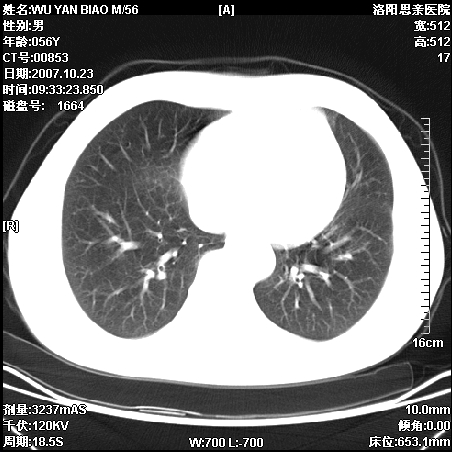

标题: CT10160:M56Y,体检发现,病人无不适,病人随访中 [打印本页]

标题: CT10160:M56Y,体检发现,病人无不适,病人随访中

后上纵隔占位,与肺交界清,宽基底附着脊柱,密度均匀,局部骨质无明确改变.

考虑;神经源性肿瘤,---起源交感n链?,不除外肠源性囊肿.

1、病灶在后纵隔脊柱旁沟内,此处是神经原性肿瘤的好发部位

2、病灶边缘光滑整齐,更说明病灶来于纵隔,由于有胸膜的包裹所以才导致这么光滑的边缘

3、病灶内的密度均匀